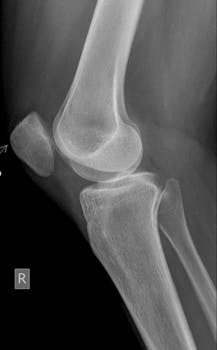

The anterior drawer sign is a crucial diagnostic test utilized by healthcare professionals to assess knee stability. It’s often performed when there’s suspicion of an anterior cruciate ligament (ACL) injury. Understanding this test and its implications can provide clarity for those experiencing knee issues or recovering from knee injuries.

The anterior drawer sign is a clinical test used primarily to evaluate the integrity of the ACL in the knee. During this procedure, the patient lies on their back with their knee bent. The examiner gently pulls the leg forward to check for excessive movement of the tibia in relation to the femur. Excessive movement could indicate a torn ACL.

The knee joint is a complex structure, and the ACL is crucial for maintaining stability. During the anterior drawer test, the examiner looks for signs of instability or a lack of resistance in the knee joint. A positive result generally suggests a compromised ACL.